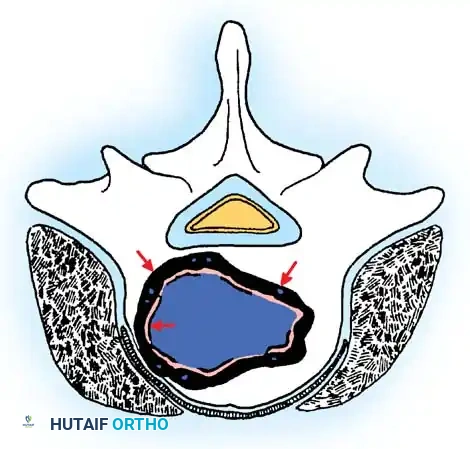

Stage 3: Aggressive Tumors

Despite being histologically benign, Stage 3 lesions (e.g., giant cell tumors, aggressive osteoblastomas) are locally destructive. They breach the tumor capsule, invade local compartments, and have a high propensity for recurrence.

Cross-sectional view of a Stage 3 aggressive benign tumor breaching the posterior vertebral wall, highlighting the necessity for wide excision to prevent local recurrence.

Wide excision—removal of the tumor with a continuous cuff of normal, healthy tissue—is the oncologic treatment of choice. A marginal excision (dissecting through the reactive pseudocapsule) leaves microscopic disease and results in unacceptably high recurrence rates.